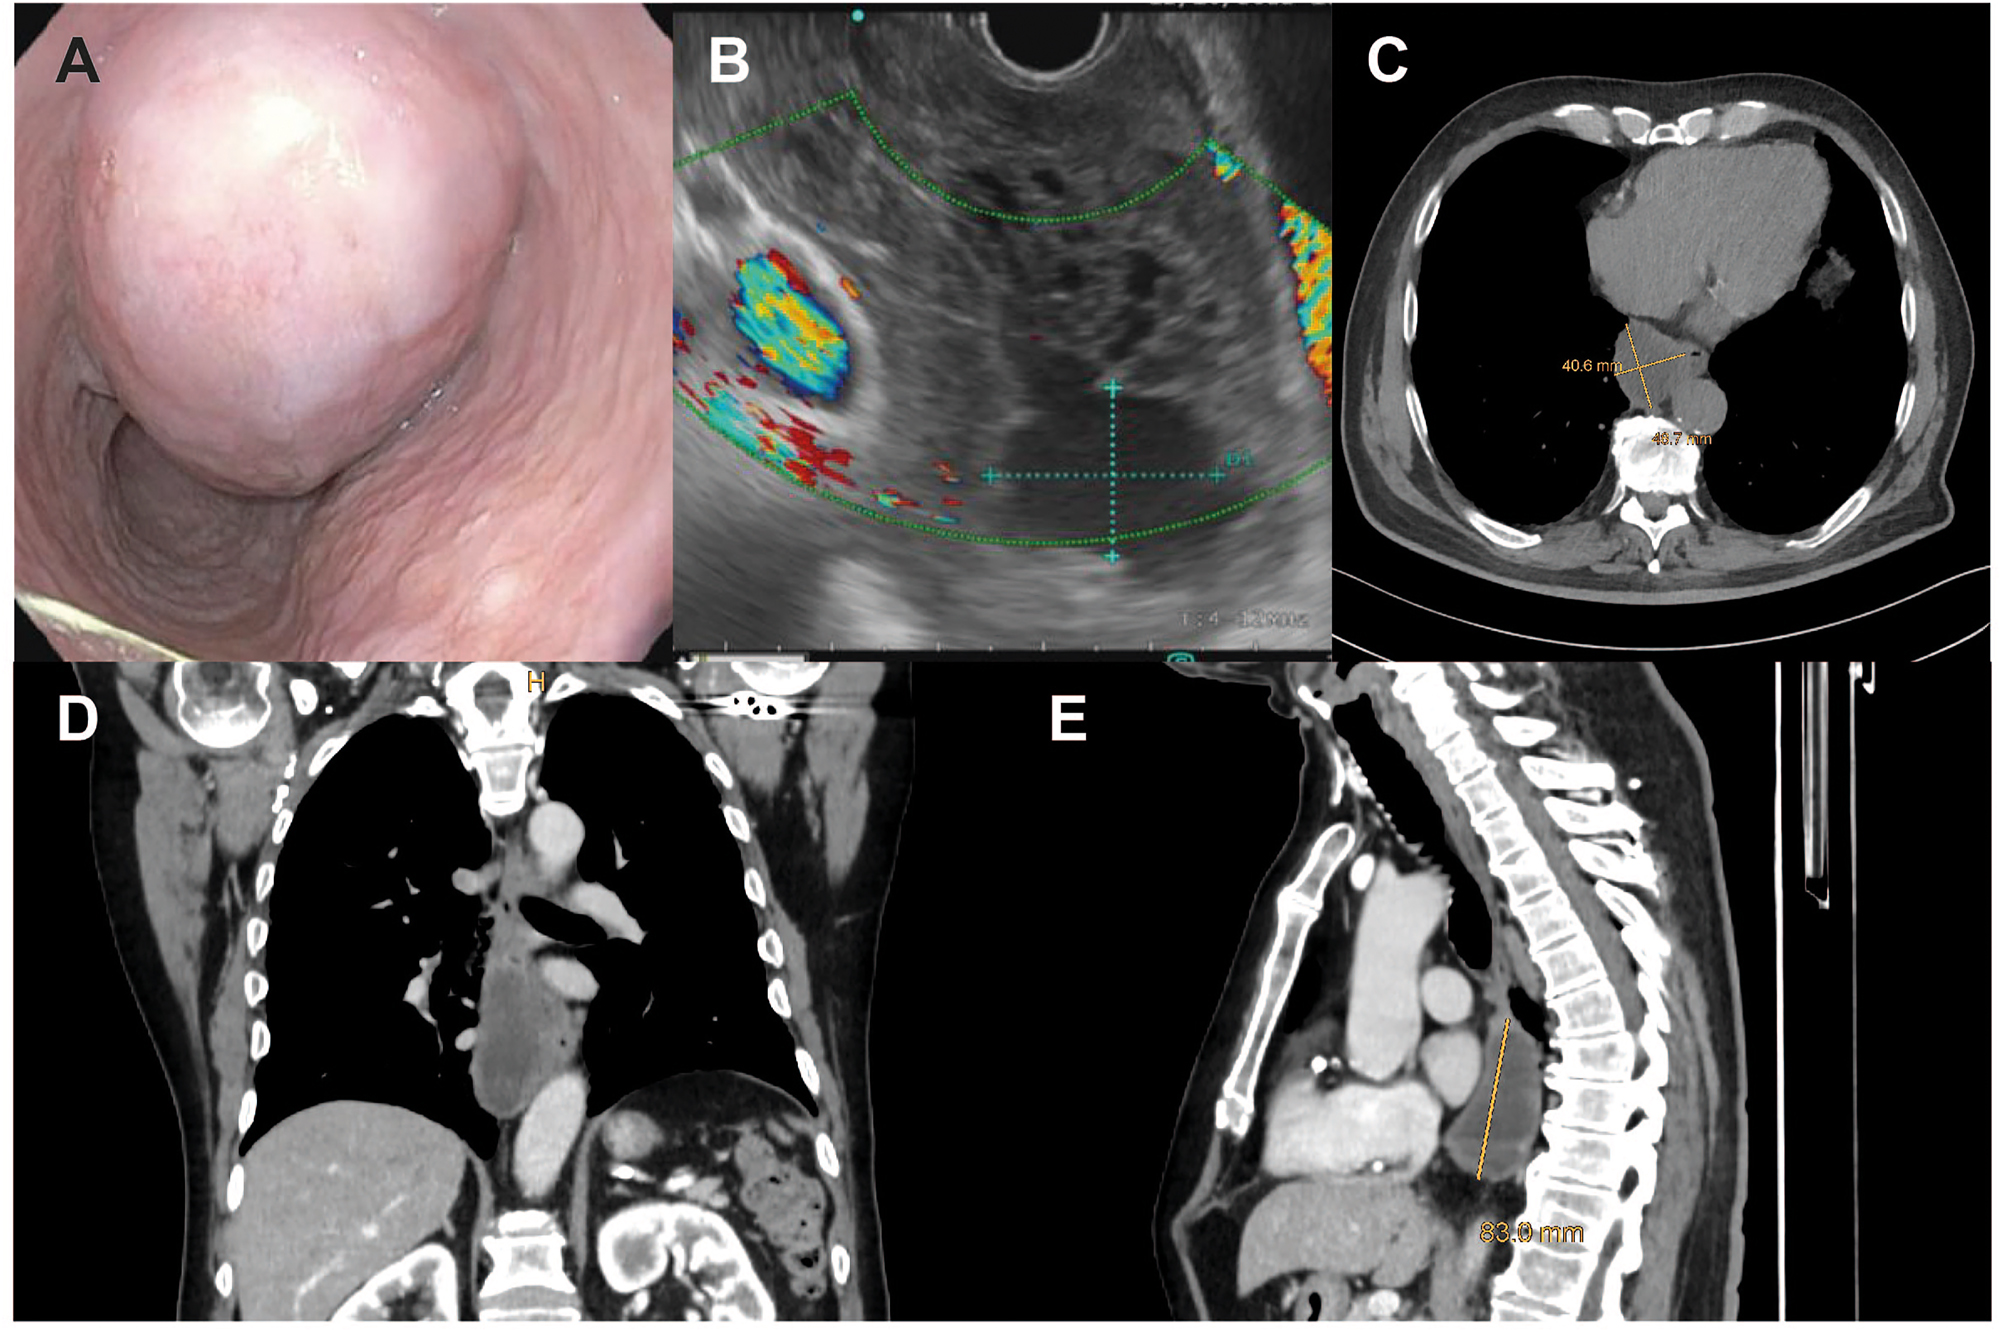

The gross appearance of the tumor is usually whitish gray, soft, encapsulated, and fish-flesh-like (Figure 1). Histologically, GIST has an overall basophilic appearance with high cellularity and mild-to-no nuclear pleomorphism on hematoxylin-eosin staining. Total of 70–80 % are composed of spindle cells, while 20–30 % are predominantly epithelioid. On immunohistochemistry, the most common markers are c-kit protein (CD117), DOG-1, and CD34, with CD117 being the most specific [33]. Mitotic activity plays a crucial role in predicting malignant potential. The National Institute of Health (NIH) has developed a classification system for GIST in general with four risk categories based on mitotic activity and size, specifically very low risk, low risk, intermediate risk, and high risk [40]. In 2016, Miettinen from the Armed Forces Institute of Pathology (termed AFIP classification), introduced a classification consisting of six groups further including the anatomic site of the primary tumor as an additional variable [41]. The most recent classification by Joensuu et al., also includes the additional risk of tumor rupture and proposes a continuous risk scale [42]. The used non-linear model accurately predicts the risk of recurrence and can be nicely visualized using prognostic contour maps. All of these risk prediction models distinguish well between high-risk and low-risk patients with resected, non-metastasized GIST [43]. Additionally, it has recently been shown that certain KIT deletion mutations in exon 11 are associated with recurrence and metastasis in eGIST [44].

Case of a male patient with a large (9 × 5 cm) esophageal GIST. Endoscopic (A) and endosonographic (B) view, as well as transverse (C), coronal (D) and sagittal (E) computed tomography planes of the tumor.